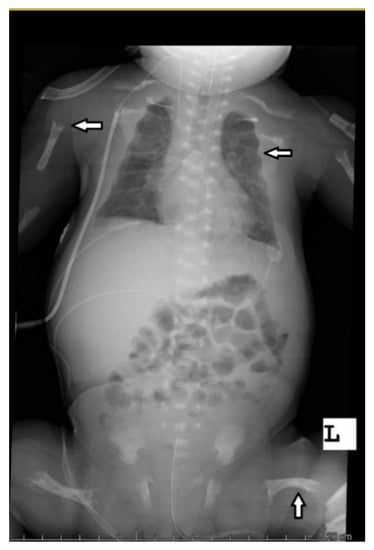

The abdominal ultrasound examinations showed the features of urolithiasis in 3/16 patients, and the X-ray examinations revealed the most common disorders of bone mineralization, abnormalities in the epiphysis of long bones–dilatation, uneven contours, bone defects, and fractures (Figure 1 and Figure 2).

Figure 1. Babygram of a patient with the perinatal disease type—disturbances in bone mineralization, bone structure, uneven edges of the epiphyses, and bone deformities after fractures.

Bone structure abnormalities observed in X-ray were characteristic and most severe for the perinatal and infantile types (they occurred in all the patients of these groups), while in other HPP types, they occurred much less frequently. A decrease in bone mineral density, assessed by densitometry, was observed in the infantile and childhood types, but it should be noted that bone demineralization was described in the perinatal type on bone radiography. In this case, DXA was not performed due to the severe patient’s condition.